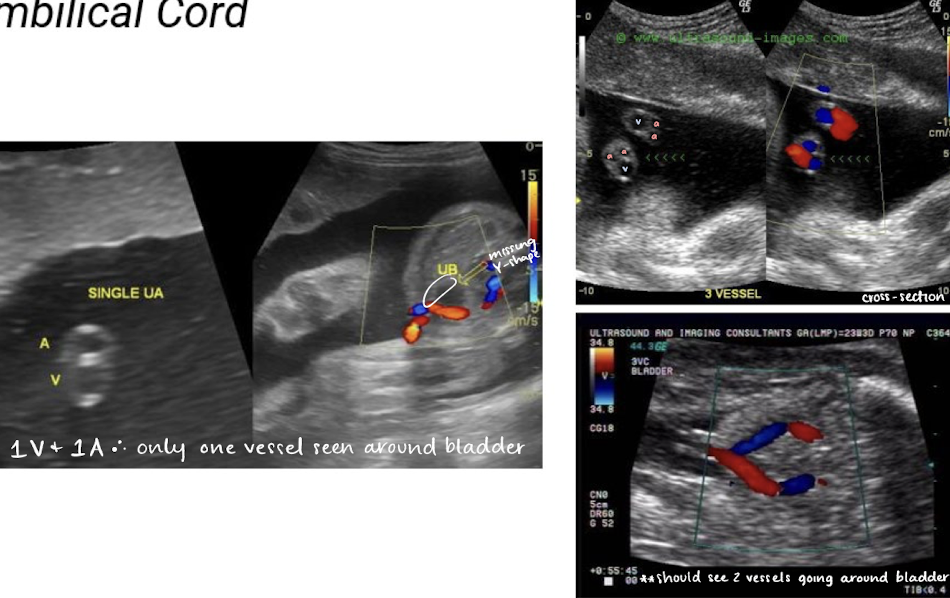

umbilical cord

umbilical cords have how many vessels

2 smaller arteries, 1 large vein

single umbilical artery (2 vessel cord) is found in 1% of singleton births

can be isolated

can be associated with congenital malformation

** umbilical arteries and vein functions opposite from typical a. and v.

umbilical arteries

2 umbilical arteries carry deoxygenated blood from fetus to placenta

umbilical arteries can be noted on either side of bladder at fetal insertion

umbilical vein

1 umbilical vein carries oxygenated blood from placenta to fetus

umbilical cord color Doppler

color Doppler is used to visualize umbilical arteries and vein

the bladder, when full, is seen between 2 umbilical arteries

umbilical cord should be images in cross section and with color Doppler at level of bladder to confirm the number of cord vessels